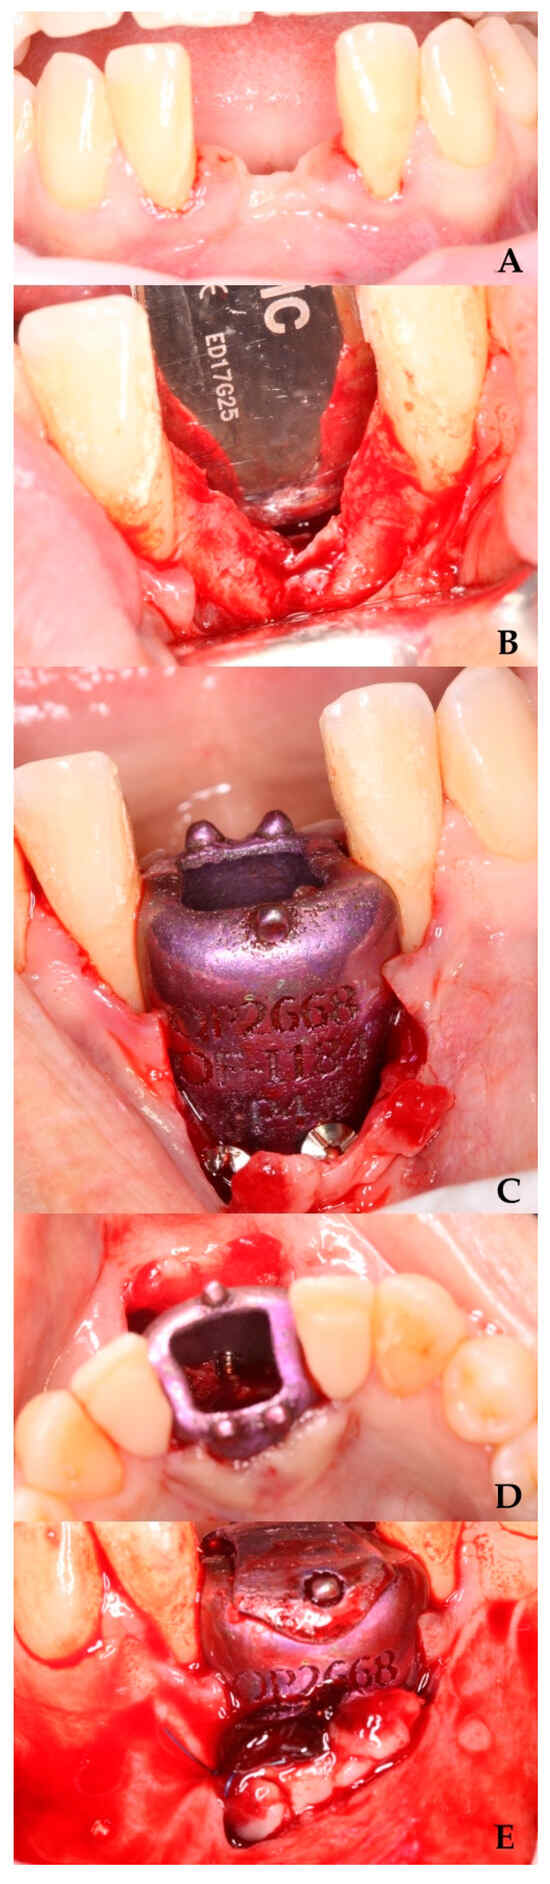

A six-month follow-up period was conducted prior to the placement of the barrier. Anesthesia was administered, the screws were removed, and the barrier was sectioned into two segments for extraction (Figure 4).

Figure 4. Barrier removal. (A) Lifting of the cover. (B) Area irrigated with physiological saline solution. (C) Barrier section. (D) Regenerated area.

3.2. Second Surgical Phase

Following a four-month healing period, implant placement was initiated under local anesthesia. A computer-guided surgical stent was utilized to achieve optimal prosthetic positioning. A bone core sample was then harvested using a trephine drill for histological analysis.

Osteotomy preparation was performed according to the planned implant dimensions (Figure 5), followed by placement of a C1 MISS implant (3.75 mm diameter × 10 mm length) in the prosthetically driven position to fulfill restorative requirements.

Figure 5. Implant placement in the regenerated area. (A) Regenerated area at 10 months. (B) Implant in the regenerated area. (C) Orthopantomography with the implant in the regenerated area.